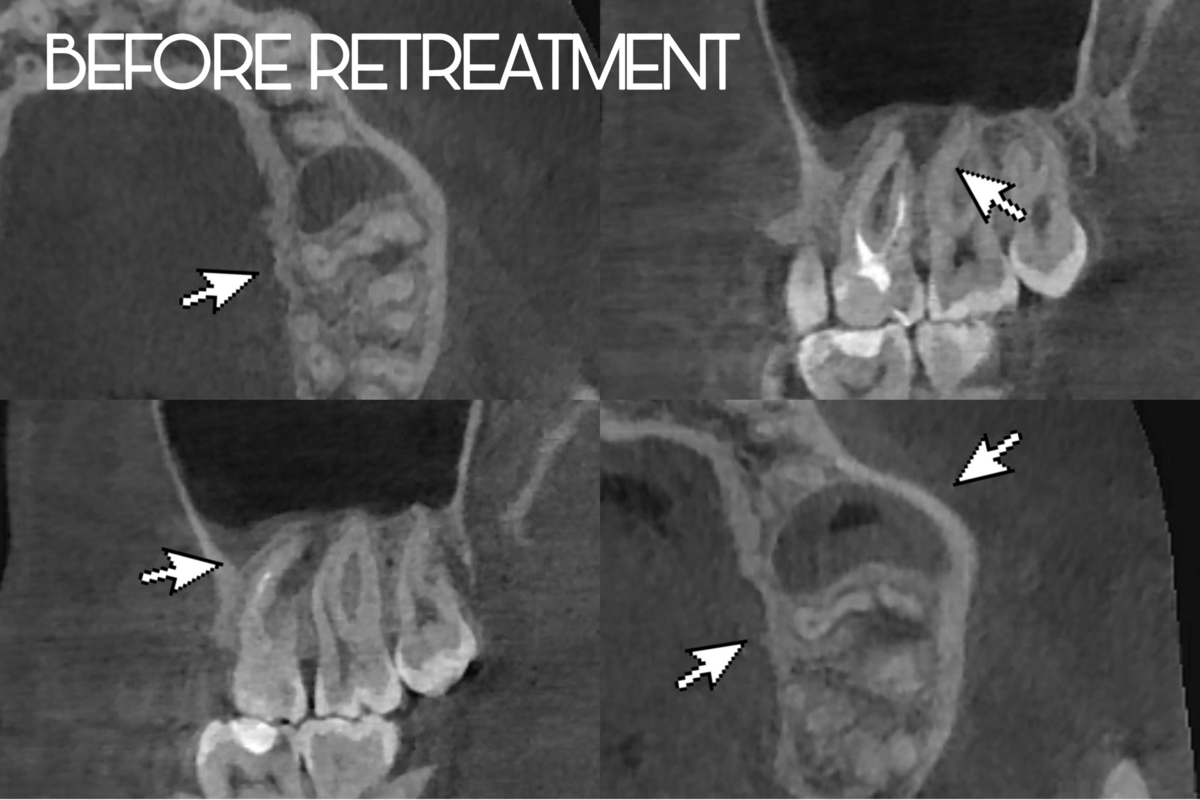

Снимок до лечения, виден патологический процесс на корнях зуба и утолщение слизистой гайморовой пазухи